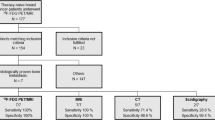

Ethics approval was obtained to access FDG-PET/CT scans of patients with stage IV non-small cell lung cancer (NSCLC) diagnosed between 2006 and 2013. The FDG-PET/CT scan was performed with a GE Discovery 710 scanner (GE Healthcare, Waukesha WI). The low dose CT was acquired prior to the PET scan in a 512 × 512 × 311 matrix with a voxel size 1.37 × 1.37 × 3.75 mm and PET images were acquired in 256 × 256 × 311 matrix with voxel size 2.7344 × 2.7344 × 3.27 mm (voxel volume = 0.02445 ml). A retrospective review of FDG-PET/CT scans of more than 30 candidate NSCLC patients was performed and nine patients with one or more metastatic bone lesions were selected for the present study based on visual inspection of co-registered low-dose CT and PET dataset using imaging software MIM (MIM-6.5; MIM Software Inc., Cleveland, OH, USA).

The SUV threshold prediction model was designed by splitting the cohort of patients into a subset of ‘development’ and ‘validation’ cohorts. The development cohort was used to determine the optimum SUV threshold for automatic detection of bone metastases. The validity of the derived optimum SUV threshold was tested on the ‘validation’ patient cohort.

Figure 1 shows the flowchart of the software developed for the detection, delineation and quantification of bone metastases using PET/CT images.